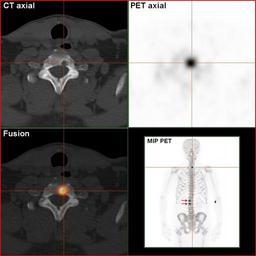

MAKE A MEME View Large Image RenalCancer-90MBq-F-18-Fluorid-PET-CT.jpg en Sodium-Fluoride-PET-Scan of a patient suffering from kidney disease with several bone matastases in the vertebral column This is the same patient as shown in the image RenalCancer-700MBq-HDP-Bone...

Keywords: RenalCancer-90MBq-F-18-Fluorid-PET-CT.jpg en Sodium-Fluoride-PET-Scan of a patient suffering from kidney disease with several bone matastases in the vertebral column This is the same patient as shown in the image RenalCancer-700MBq-HDP-BoneScinti-3hpi jpg The osteolytic metastasis in the neck is clearly visible de Natriumfluorid-PET/CT-Scan eines Patienten mit metastasiertem Nierenkarzinom Dies ist der selbe Patient wie im Bild RenalCancer-700MBq-HDP-BoneScinti-3hpi jpg Die osteolytische Knochenmetastase in der Halswirbelsäule ist klar dargestellt own Hg6996 2011-03-14 Mit freundlicher Genehmigung Südwestdeutsches PET-Zentrum Stuttgart am Diakonie-Klinikum Stuttgart Cc-zero Positron emission tomography